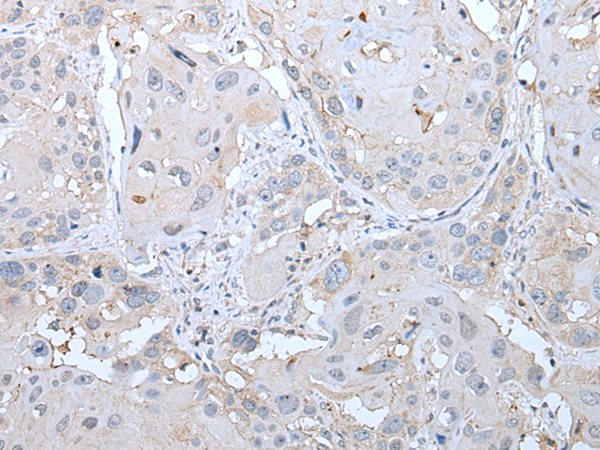

分类: 科研抗体货号: P12760别名: HHF5; CD220应用: IHC反应种属: Human, Mouse, Rat